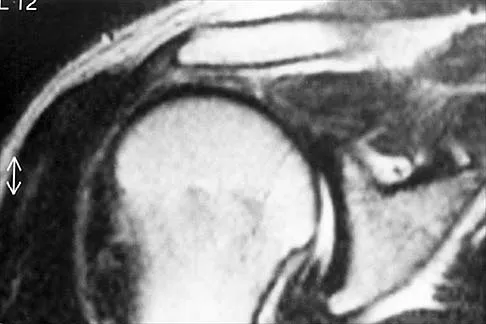

A 55-year-old woman with a 15-year history of systemic lupus erythematosus has had left shoulder pain for the past 3 months. She reports that the pain has grown progressively worse over the past few months, and her shoulder function is severely limited. She is presently being treated with azathioprine and has used corticosteroids in the past. AP and axillary radiographs are shown in Figures 19a and 19b, and MRI scans are shown in Figures 19c and 19d. Which of the following forms of management will yield the most predictable pain relief and return of shoulder function?

Explanation